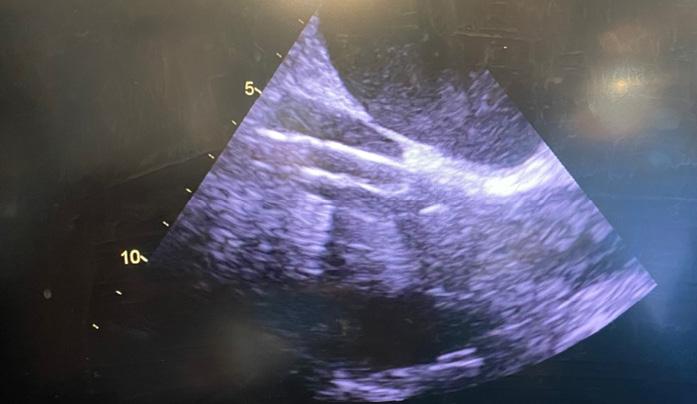

Pacientul este plasat în decubit dorsal cu umărul drept ușor ridicat; este anestezi at și intubat cu sondă dublu lumen care să permită ventilația selectivă pulmonară. Se introduce o sondă de ecocardiografie tran sesofagiană (ETE) cu ajutorul căreia se confirmă diagnosticul preoperator și me canismul patologiei mitrale, se ghidează canularea periferică pentru circulație ex tracorporală (CEC) și se evaluează funcția cadiacă și calitatea gestului asupra VMi. Pacientul este rotat 30 grade către stânga, efectuându-se o toracotomie antero-la terală de 5-7 cm în al IV-lea spațiu inter costal. Rotirea pacientului către stânga nu este obligatorie, multe centre renunțând la această abordare, din cauză că inima se îndepărtează de toracele drept. În schimb, este important ca brațul drept să fie flectat la 120 grade și în ușoară abducție, pentru a se îndepărta de viitoarea incizie (Fig.1,2).

zitive de etanșeizare vasculară tip Proglide. ETE confirmă prezența ghidului în lumenul aortei descendente toracice (Fig.6), preve nind cea mai de temut complicație a canu lării periferice: disecția retrogradă de aortă.

Abia după ce se confirmă localizarea ghidului, se avansează canula arterială femurală. După canularea arterială se continuă cu cea venoasă. Indiferent dacă se utilizează o canulă “single-stage” sau “dual-stage”, ghidul trebuie avansat și ve rificat în atriul drept (AD) până la nivelul venei cave superioare (VCS) (Fig.7).

Se avansează apoi cu canula venoasă; în cazul canulării VCI se verifică ecogra fic și tactil (dacă se poate) prezența canu lei la joncțiunea VCI cu AD (Fig.8).